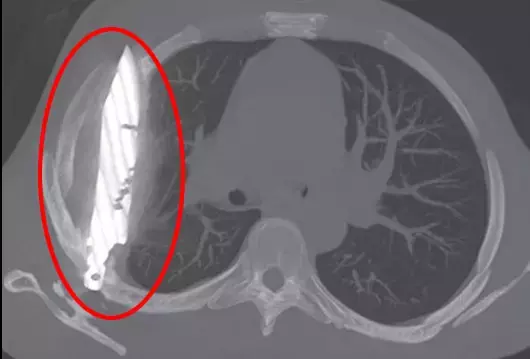

Tanzanya‘da 44 yaşındaki bir adam, sağ memesinin altından iltihap akması şikâyetiyle hastaneye gitti. Doktorlar ilk muayenede herhangi bir ağrı, nefes darlığı, öksürük ya da ateş bulgusuna rastlamadı. Ancak yapılan röntgen, herkesin ağzını açık bıraktı: Adamın göğsünde tam sekiz yıldır saplı duran bir bıçak vardı.

Hasta, yıllar önce yaşadığı şiddetli bir kavga sırasında yüzünden, sırtından, göğsünden ve karnından yaralandığını, o zaman tedavi gördüğünü söyledi. O günden beri ciddi bir sağlık sorunu yaşamamıştı. Fakat son günlerde fark ettiği iltihap nedeniyle doktora başvurunca, yıllardır göğsünde “unutulmuş” bıçak ortaya çıktı.

Bıçak, sağ kürek kemiğinden girip hayati organlara zarar vermeden göğüste kalmıştı. Ameliyatla çıkarılan bıçakla birlikte ölü doku temizlendi. Hasta yoğun bakımda bir gün, normal serviste ise 10 gün kaldı. Doktorlar, takip kontrollerinde hastanın tamamen iyileştiğini duyurdu.